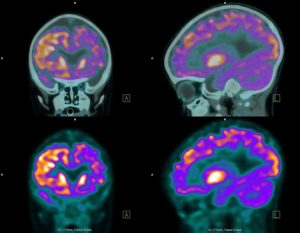

A total of 43 women between the ages of 40 to 60 participated in the study, all of which went under positron emission tomography (PET) scanning. This type of imaging study uses a special dye that has radioactive tracers that light up once absorbed by various tissues. It can allow physicians to measure blood flow, oxygen use, and glucose metabolism.

PET scanning revealed that the areas of the brain where energy use had dropped were similar to the areas affected in people with Alzheimer’s disease. However, the women in this study were not followed to see if they developed the neurodegenerative disease or not.